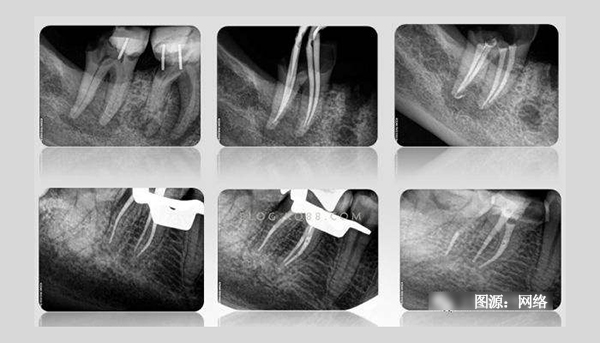

有根管治療史的患者都知道,在根管治療過程中需要反復(fù)拍攝多次X光片。一般說來,完成一顆牙的根管治療至少需要3張X光片:術(shù)前X光片、術(shù)中X光片、術(shù)后X光片。

術(shù)前X線片反映患牙及牙周組織的客觀情況—根管長度、根尖周牙槽骨密度等,目的主要是幫助牙醫(yī)了解患牙的病變范圍、牙根情況、根管數(shù)目以及根尖周病變情況,根管是否存在鈣化,幫助醫(yī)生判斷患牙的預(yù)后以及根管治療的難度,是牙科治療的依據(jù)。

術(shù)中需要對根管預(yù)備情況進(jìn)行檢查,主要是輔助測量根管長度,看根管預(yù)備是否到位,牙齒里面的神經(jīng)是否清理干凈。對于難度較大者需要一邊進(jìn)行根管預(yù)備一邊插針拍X線片,以監(jiān)測根管預(yù)備的方向和程度以求良好的治療效果。

術(shù)后X線片是為了觀察根管治療是否徹底,根管內(nèi)充填物是否合適,判斷根管治療充填的質(zhì)量是否到位。術(shù)后拍攝X線片,有助于醫(yī)生對治療效果的判斷,如果治療結(jié)果不滿意可及時更正,以免出現(xiàn)不必要的復(fù)診。根管治療術(shù)后拍X線片片已成為檢驗根管治療質(zhì)量的手段之一,是根管治療規(guī)范化操作的一部分。